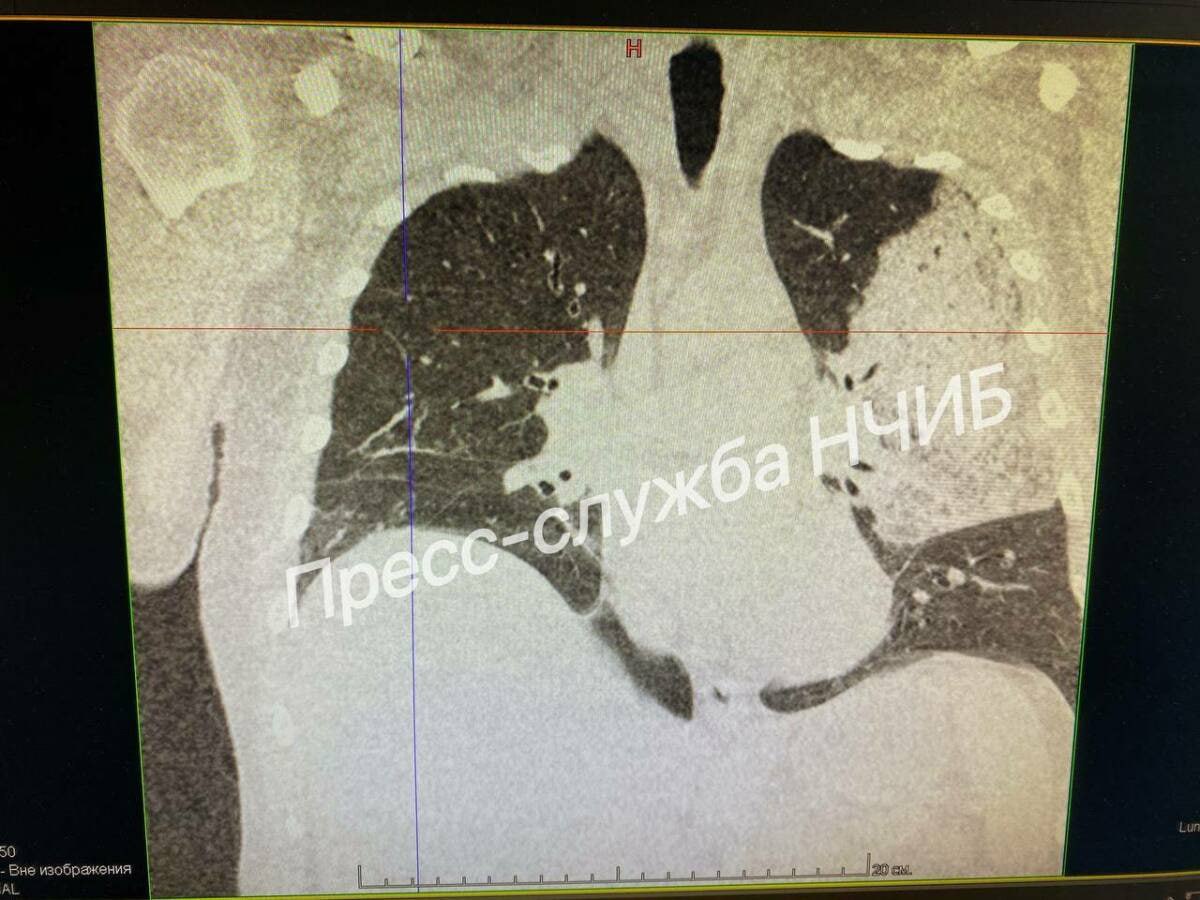

Врачи Набережночелнинской инфекционной больницы спасли мужчину с тяжелым поражением легких

Для поддержания жизненных функций врачи применили интенсивную терапию. На восьмой день была выполнена трахеостомия, после чего появились первые признаки улучшения.

«Он провёл на ИВЛ десять дней. Изначально мы не давали оптимистичных прогнозов, но благодаря командной работе и грамотному лечению удалось добиться положительной динамики», - отметил Ришат Хакимов.

Постепенно пациента отключили от аппарата искусственной вентиляции легких, перевели в палату, а затем выписали.